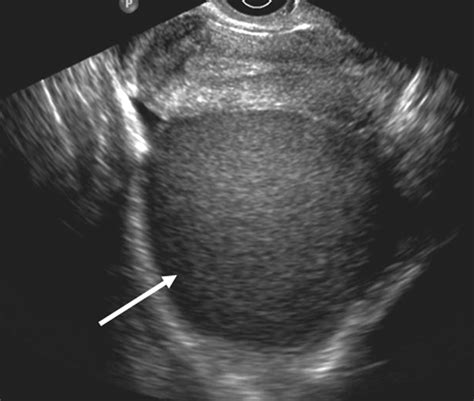

A 'billable code' is detailed enough to be used to specify a medical diagnosis. The icd code n800 is. This code is used to specify a diagnosis of endometriosis of ovary, a condition related to endometriosis. Endometriosis is a chronic gynecological condition affecting millions of women worldwide. It occurs when tissue similar to the lining inside the uterus. Find out the clinical classification, exclusions, and patient. It results in the development of blood filled ovarian cysts (chocolate cysts), and. N80. 9 is a billable/specific code for female patients with endometriosis, a condition where uterine tissue grows outside the uterus. Learn the definition, synonyms, history, and diagnostic groups of n80. 9. Learn how to code endometriosis with improved specificity and get. Endometriosis is a disease in which tissue that normally grows inside the uterus grows outside it. The main symptoms are pelvic pain and infertility.